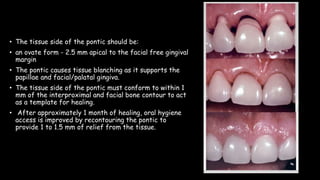

The document discusses pontic design for fixed dental prostheses. It covers pretreatment assessment of residual ridge contours, classifications of ridge deformities, surgical modification techniques, and ideal requirements for pontics. Pontic designs are classified based on their shape and materials. Factors in pontic selection include esthetics and oral hygiene. Common designs for anterior and posterior regions are described, including sanitary, ovate, and saddle pontics. Biological considerations for pontic design involve maintaining the residual ridge, abutment teeth, and supporting tissues.